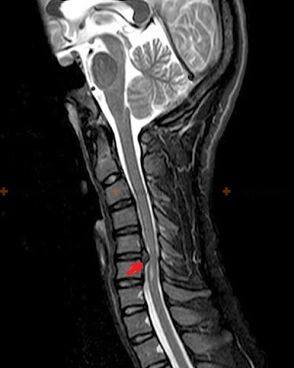

Osteochondrosis is an X-ray diagnosis, because a detailed clinical picture is available only at the moment of severity, while changes in the spine can occur with a person's subjective well-being.Without an X-ray examination, we can only talk about suspected osteochondrosis, because the same symptoms can be caused by other diseases (myositis, vertebral neoplasm, etc.).

To diagnose osteochondrosis, the following research methods are used: Radiography (better with functional tests), MSCT and MRI.The latter study is the most preferred due to the fact that it allows one to clearly describe the state of the intervertebral structure.

The presence of the changes described above, as well as changes in the structure of the intervertebral disc, detected by MSCT and MRI, serve as reliable signs that confirm the presence of osteochondrosis.